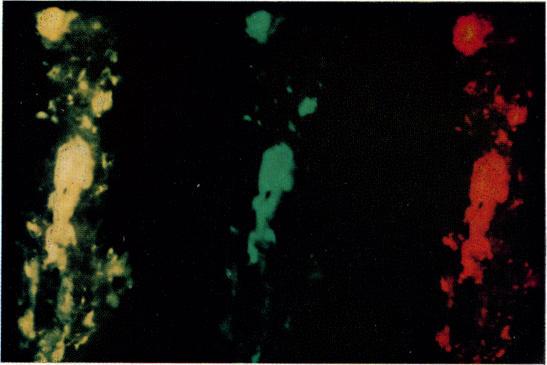

An immunofluorescence mixed staining technique for the detection of IgG-rheumatoid factor and IgG-beta-1C complexes in tissues.

A mixed immunofluorescent staining method for the detection of immune complexes in the tissues is described. This method demonstrated the presence of IgG-rheumatoid factor and IgG-β complexes in synovial membrane from patients with rheumatoid arthritis.